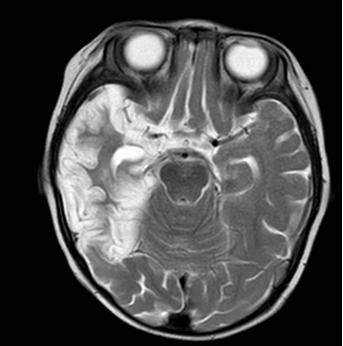

图1 单纯疱疹病毒脑炎,箭头所示为颞岛叶皮层坏死、脑软化及部分胶质增生

◇ 影像学检查:头颅CT、磁共振等。